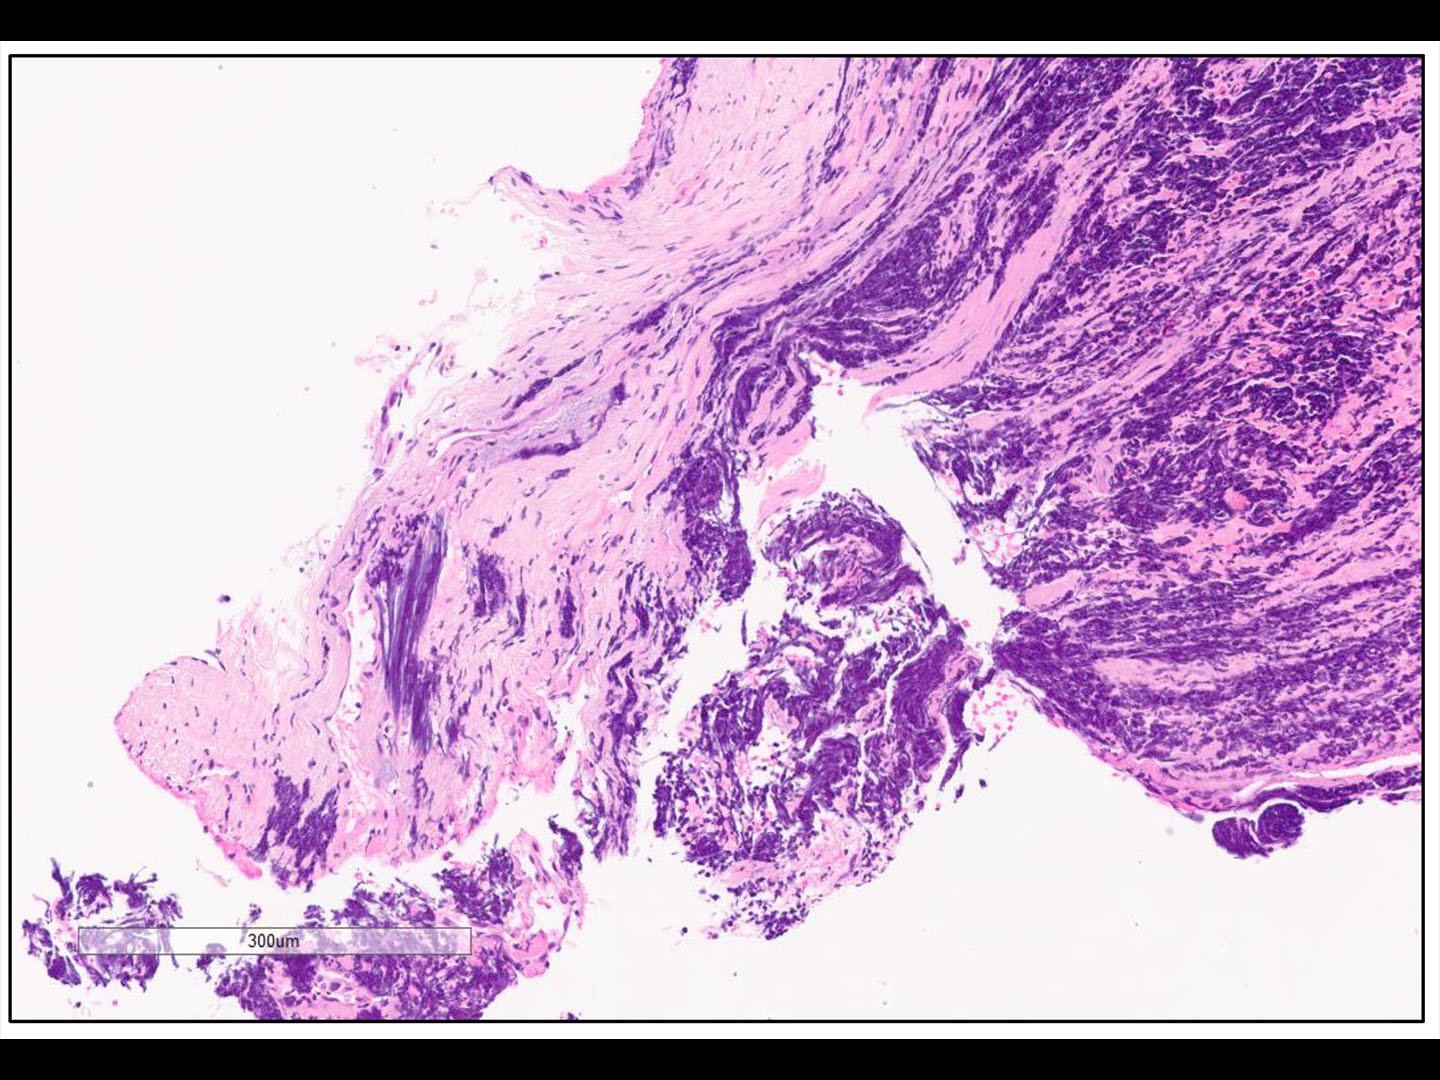

Diagnostik > Bildgebung

Rundherd: Wahrscheinlichkeit für Malignität ↗ bei > 40-Jährigen und Rauchern

Die Wahrscheinlichkeit, dass einem Lungenrundherd im Röntgen-Thx etwas Malignes zugrunde liegt, ist deutlich höher bei über 40-Jährigen und Rauchern.

Gewisse Kriterien des Rundherdes deuten auf einen malignen Tumor hin.